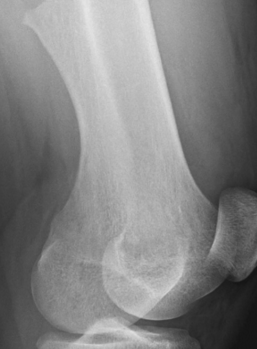

<p>An 18-year-old boy presents with pain and swelling of his left thigh that developed suddenly 2 days earlier. He denies any recent traumato the site, fevers, or weight loss.</p>